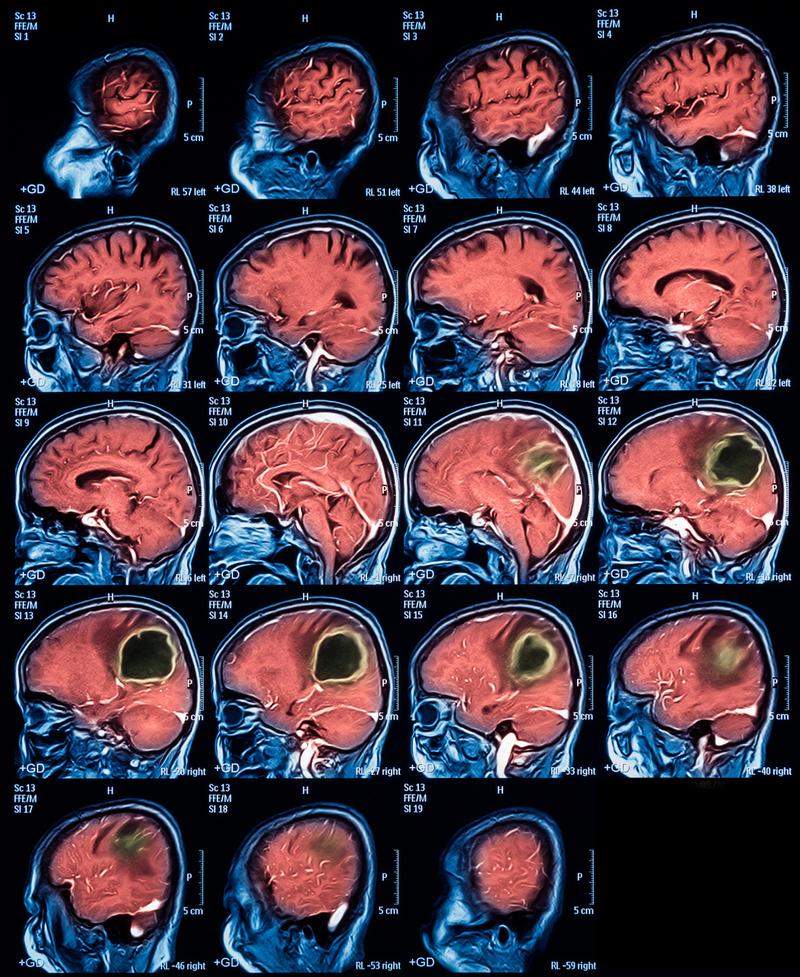

查出脑梗后,接下来该怎么办?

(图片来源网络,侵删)

立即就医,争分夺秒:

- 脑梗死是急症,治疗有“时间窗”限制,一旦确诊或高度怀疑,需要尽快进行溶栓或取栓等治疗,以挽救濒临死亡的脑组织,减少后遗症。

明确病因(至关重要):

- 治疗只是第一步,更重要的是找到导致血管堵塞的根本原因,以防止复发,医生会安排一系列检查,包括:

- 头颈部CTA/MRA(CT血管造影/磁共振血管造影):查看大脑和颈部的血管有无狭窄、斑块或闭塞。

- 心脏检查(如心电图、心脏超声、24小时动态心电图):排查心源性栓塞(如房颤、心瓣膜病)等常见原因。

- 血液检查:检查血脂、血糖、同型半胱氨酸等指标。

急性期治疗:

- 静脉溶栓:在发病后4.5小时内(部分患者可延长至6小时),使用溶栓药物(如阿替普酶)将堵塞血管的血栓溶解,这是目前最有效的治疗手段之一。

- 动脉取栓:对于大血管堵塞的患者,如果超过溶栓时间窗(通常在6-24小时内),可以通过介入手术将血栓直接取出,恢复血流。

长期康复与二级预防:

- 康复治疗:根据后遗症情况,进行针对性的康复训练,包括物理治疗(PT)、作业治疗(OT)、言语治疗(ST)等,最大限度地恢复功能。

- 药物治疗:长期服用抗血小板药物(如阿司匹林、氯吡格雷)或抗凝药物(如华法林、新型口服抗凝药),以及控制血压、血糖、血脂的他汀类药物等。

- 生活方式改变:戒烟限酒、健康饮食(低盐低脂)、规律运动、控制体重、保持良好心态。